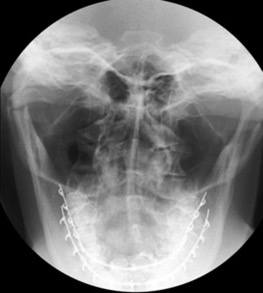

5. INCIDENCE DE CALDWELL'S = FACE HAUTE

(ROCHERS DANS LE 1/3 INF. DES ORBITES)

Etude des sinus frontaux et ethmoïdaux